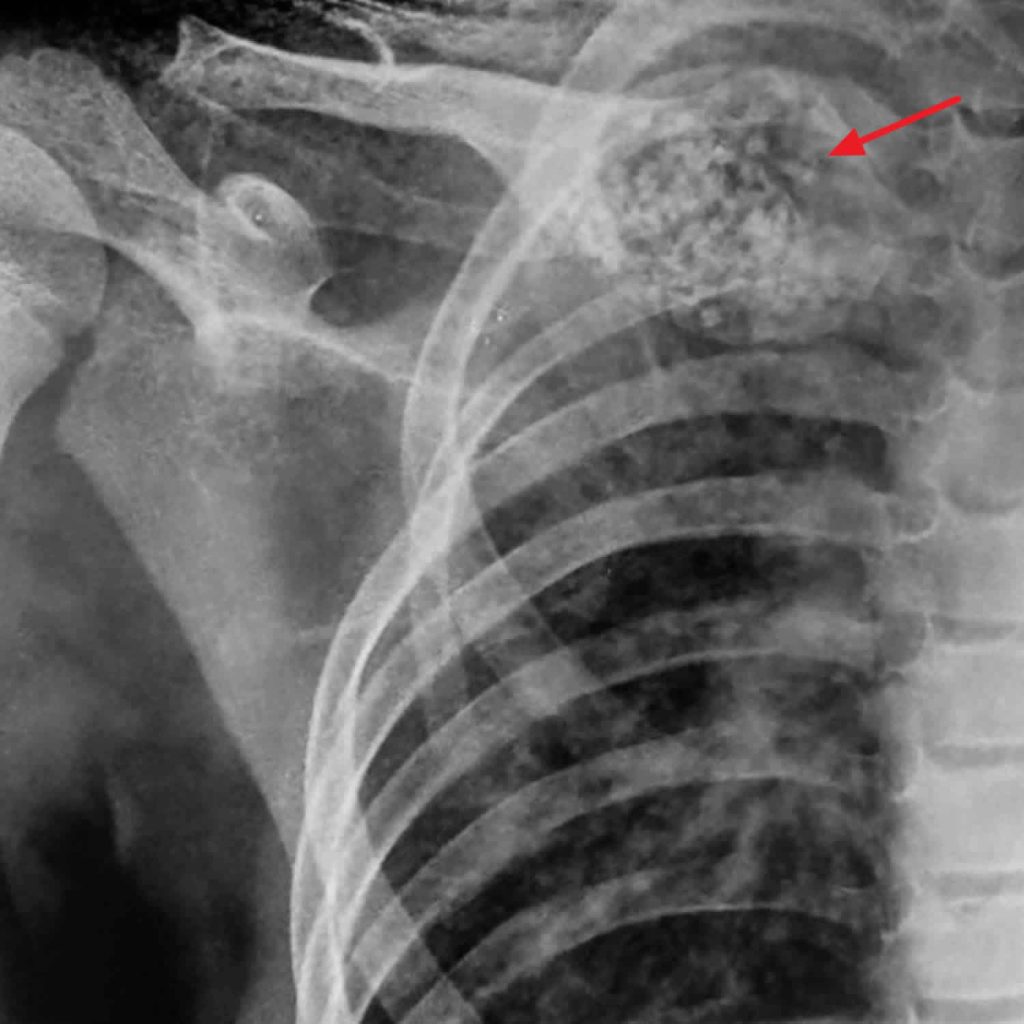

Unicameral bone cyst in a child’s humerus. Download Scientific Diagram Are Bone Cysts Common What is a subchondral bone cyst? Unicameral [simple] bone cysts (ubc): Most go away on their own over time. Bone cysts are pockets of fluid in the bones that are common in children and teens as they grow. Some unicameral bone cysts may spontaneously resolve without medical intervention. While there are often no symptoms, bone cysts can cause the bone. Are Bone Cysts Common.